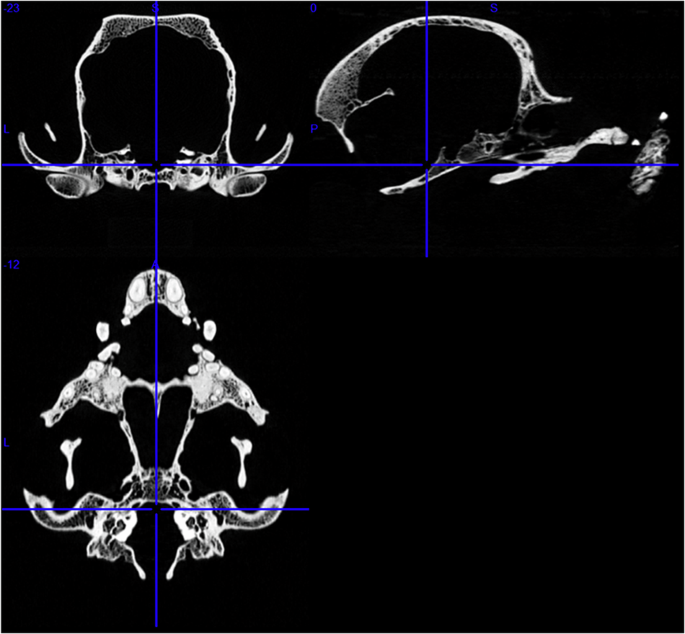

Skulls were transported to Moritz Kaposi Teaching Hospital Dr. Jozsef Baka Diagnostic, Radiation Oncology, Research and Teaching Center (Medicopus Nonprofit Ltd.) for the scanning procedure. We used a medical CT device (Siemens Somatom Definition AS+ CT, Siemens, Erlangen, Germany), and we selected a setting on the scanner that provided the best image quality with an Ultra High Resolution (UHR) protocol. Acquisition parameters were set as: 200 mAs exposure, 140 kV tube voltage, 16 × 0.6 mm collimation, and spiral data collection with 0.85 pitch factor to digitize the bones (Fig. 1). The name of this specific Siemens’ examination setting protocol is “UHR,” which stands for “ultra-high resolution”. This setting is applied to small examination areas such as the human inner ear and optic nerve imaging. Using this setting resulted in a longer imaging duration and higher radiation exposure, but considering the technical possibilities, it produced the best possible contrast ratios and spatial resolution. The benefit of using the medical CT with the UHR option was the time optimization for scanning a large number of specimens. In contrast to using an industrial micro-CT scanner, where the scanning process of one skull takes about 40–45 minutes (including scanning and reconstruction), the speed of the medical CT was approximately 5-6 minutes per skull. In some cases, a piece of polyurethane foam was placed under the skull (below the basioccipital bone) to stabilize and straighten its position during scanning.